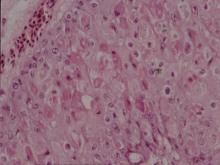

皮膚:皮膚上皮細胞呈增生及氣球樣變性,在腫脹之上皮細胞質內可見大小不一圓形

嗜酸性包涵體(圖3,4)。2.